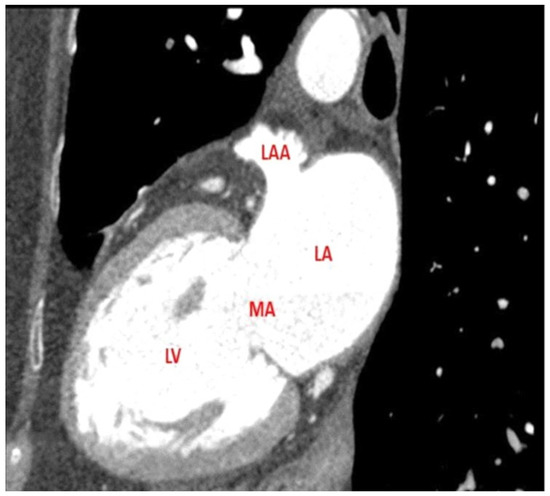

3.3. Thrombus Detection